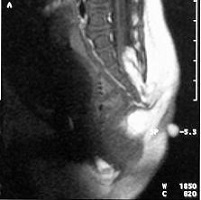

La espina bífida oculta está formada por las malformaciones como los lipomas, senos dérmicos, diastematomielia, etc. que anclan la médula. Se operan con técnicas microquirúrgicas antes del año de vida.